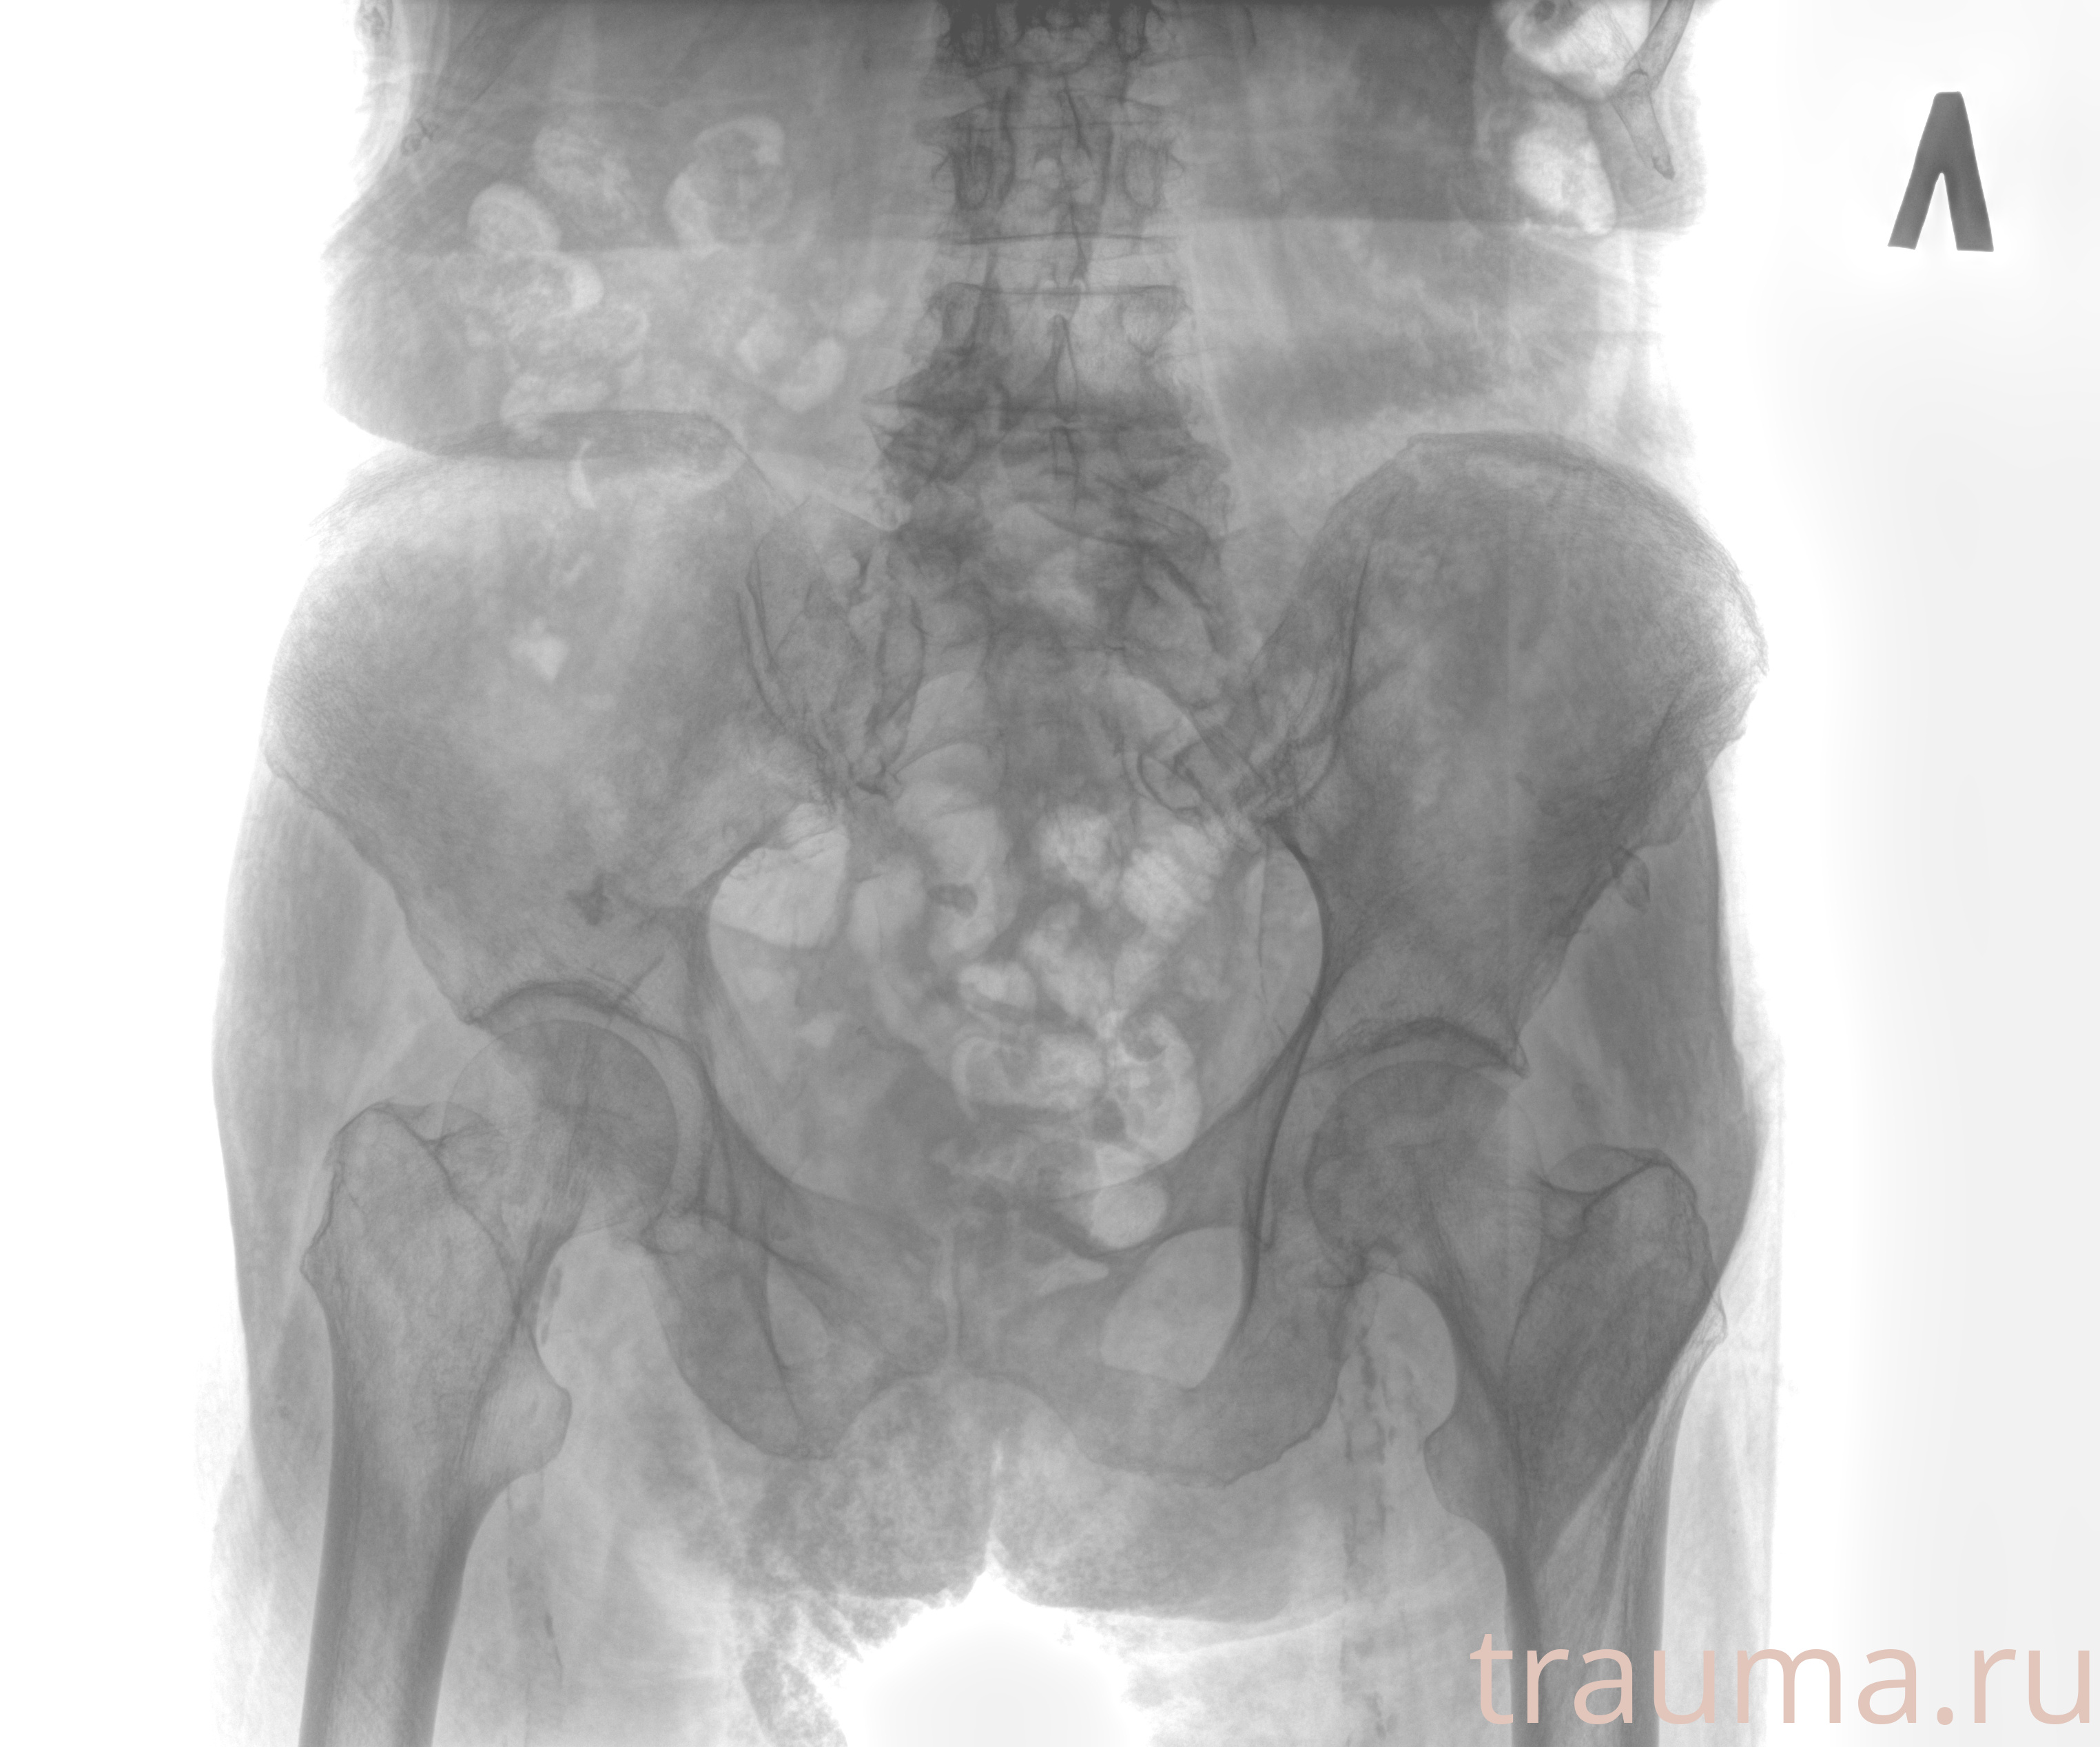

Рентгенограммы

Рентген на дому: по вашему адресу приезжает врач-рентгенолог, травматолог-ортопед с мобильным рентгеновским аппаратом, проводит диагностику травмы или заболевания, делает необходимые рентгенограммы, дает рекомендации по дальнейшему лечению. Получить качественные снимки в домашних условиях возможно благодаря уникальной методике, разработанной МосРентген Центром для института  Склифосовского